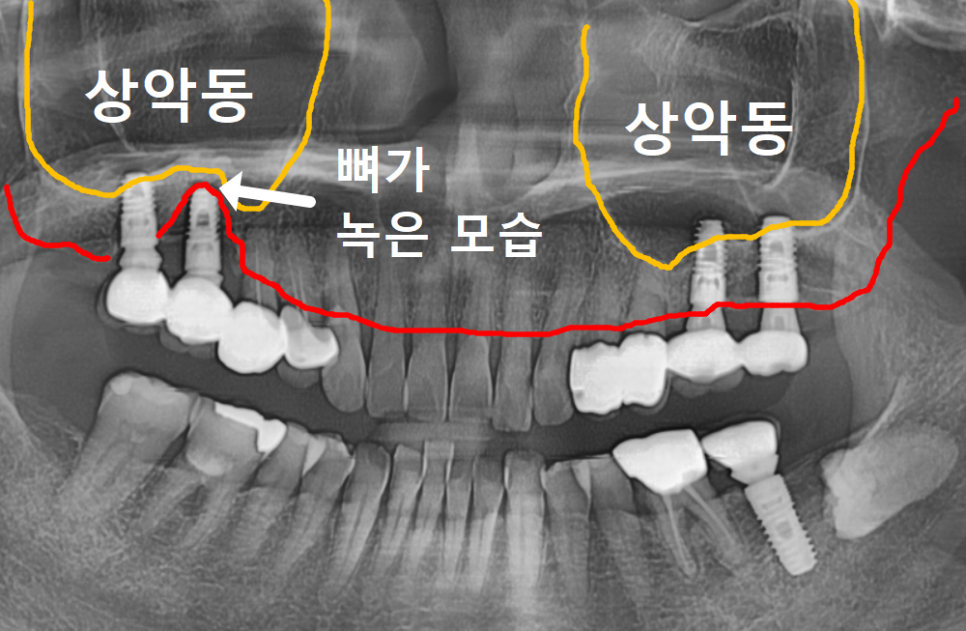

엑스레이를 찍어보니

임플란트 나사를 단단히 잡고 있어야 할

잇몸 뼈가 염증 때문에

까맣게 녹아내려 있었습니다.

231103

흔히 말하는 '임플란트 주위염'이

심각하게 진행된 상태였죠.

CT를 이리저리 돌려보며 뼈를 분석해 보니,

바깥쪽(볼 쪽) 뼈는 많이 녹았지만

안쪽(입천장 쪽) 뼈는 비교적 두껍고 튼튼하게 남아있었어요.